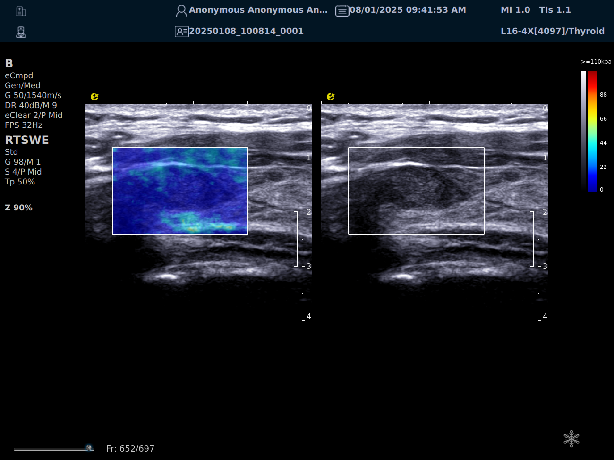

实时剪切波弹性成像

评估组织的软硬,并且提供定量数值,从而提示组织的良恶性。

image.png

鉴别诊断、精准分级、定量评价、穿刺引导、疗效评估、随访观察

恶性占位常常向周边组织进行侵润及扩散,二维很难观察到浸润部分的边界。使用实时剪切波成像能够对占位及周边组织进行硬度评估,通过颜色编码来区分不同组织的硬度信息,直观的观察占位组织的边界信息,更方便区分占位组织和正常组织的边界,准确评估消融范围。